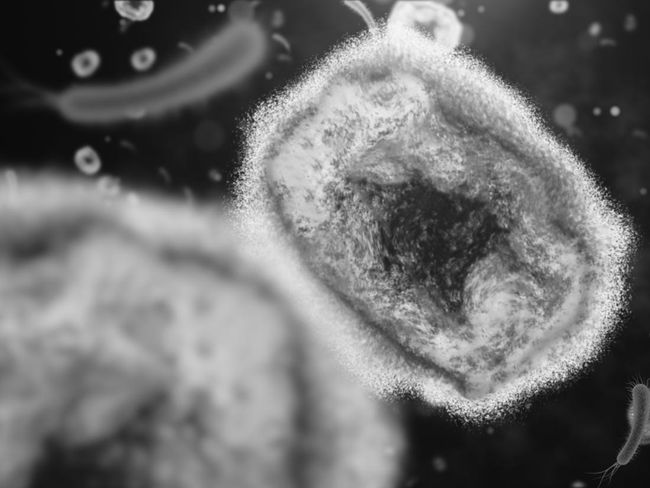

Monkeypox virus. Foto: Getty Images/iStockphoto/kontekbrothers